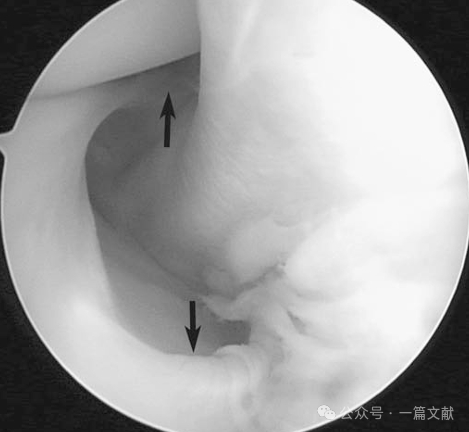

关节镜下腘肌腱走行:当腘肌腱穿行至腘肌裂孔时,通过前下、后上及后下三组腘肌半月板束附着于外侧半月板。这些半月板束形成"轮箍样"结构,将腘肌腱与腘肌裂孔处的外侧半月板紧密连接。